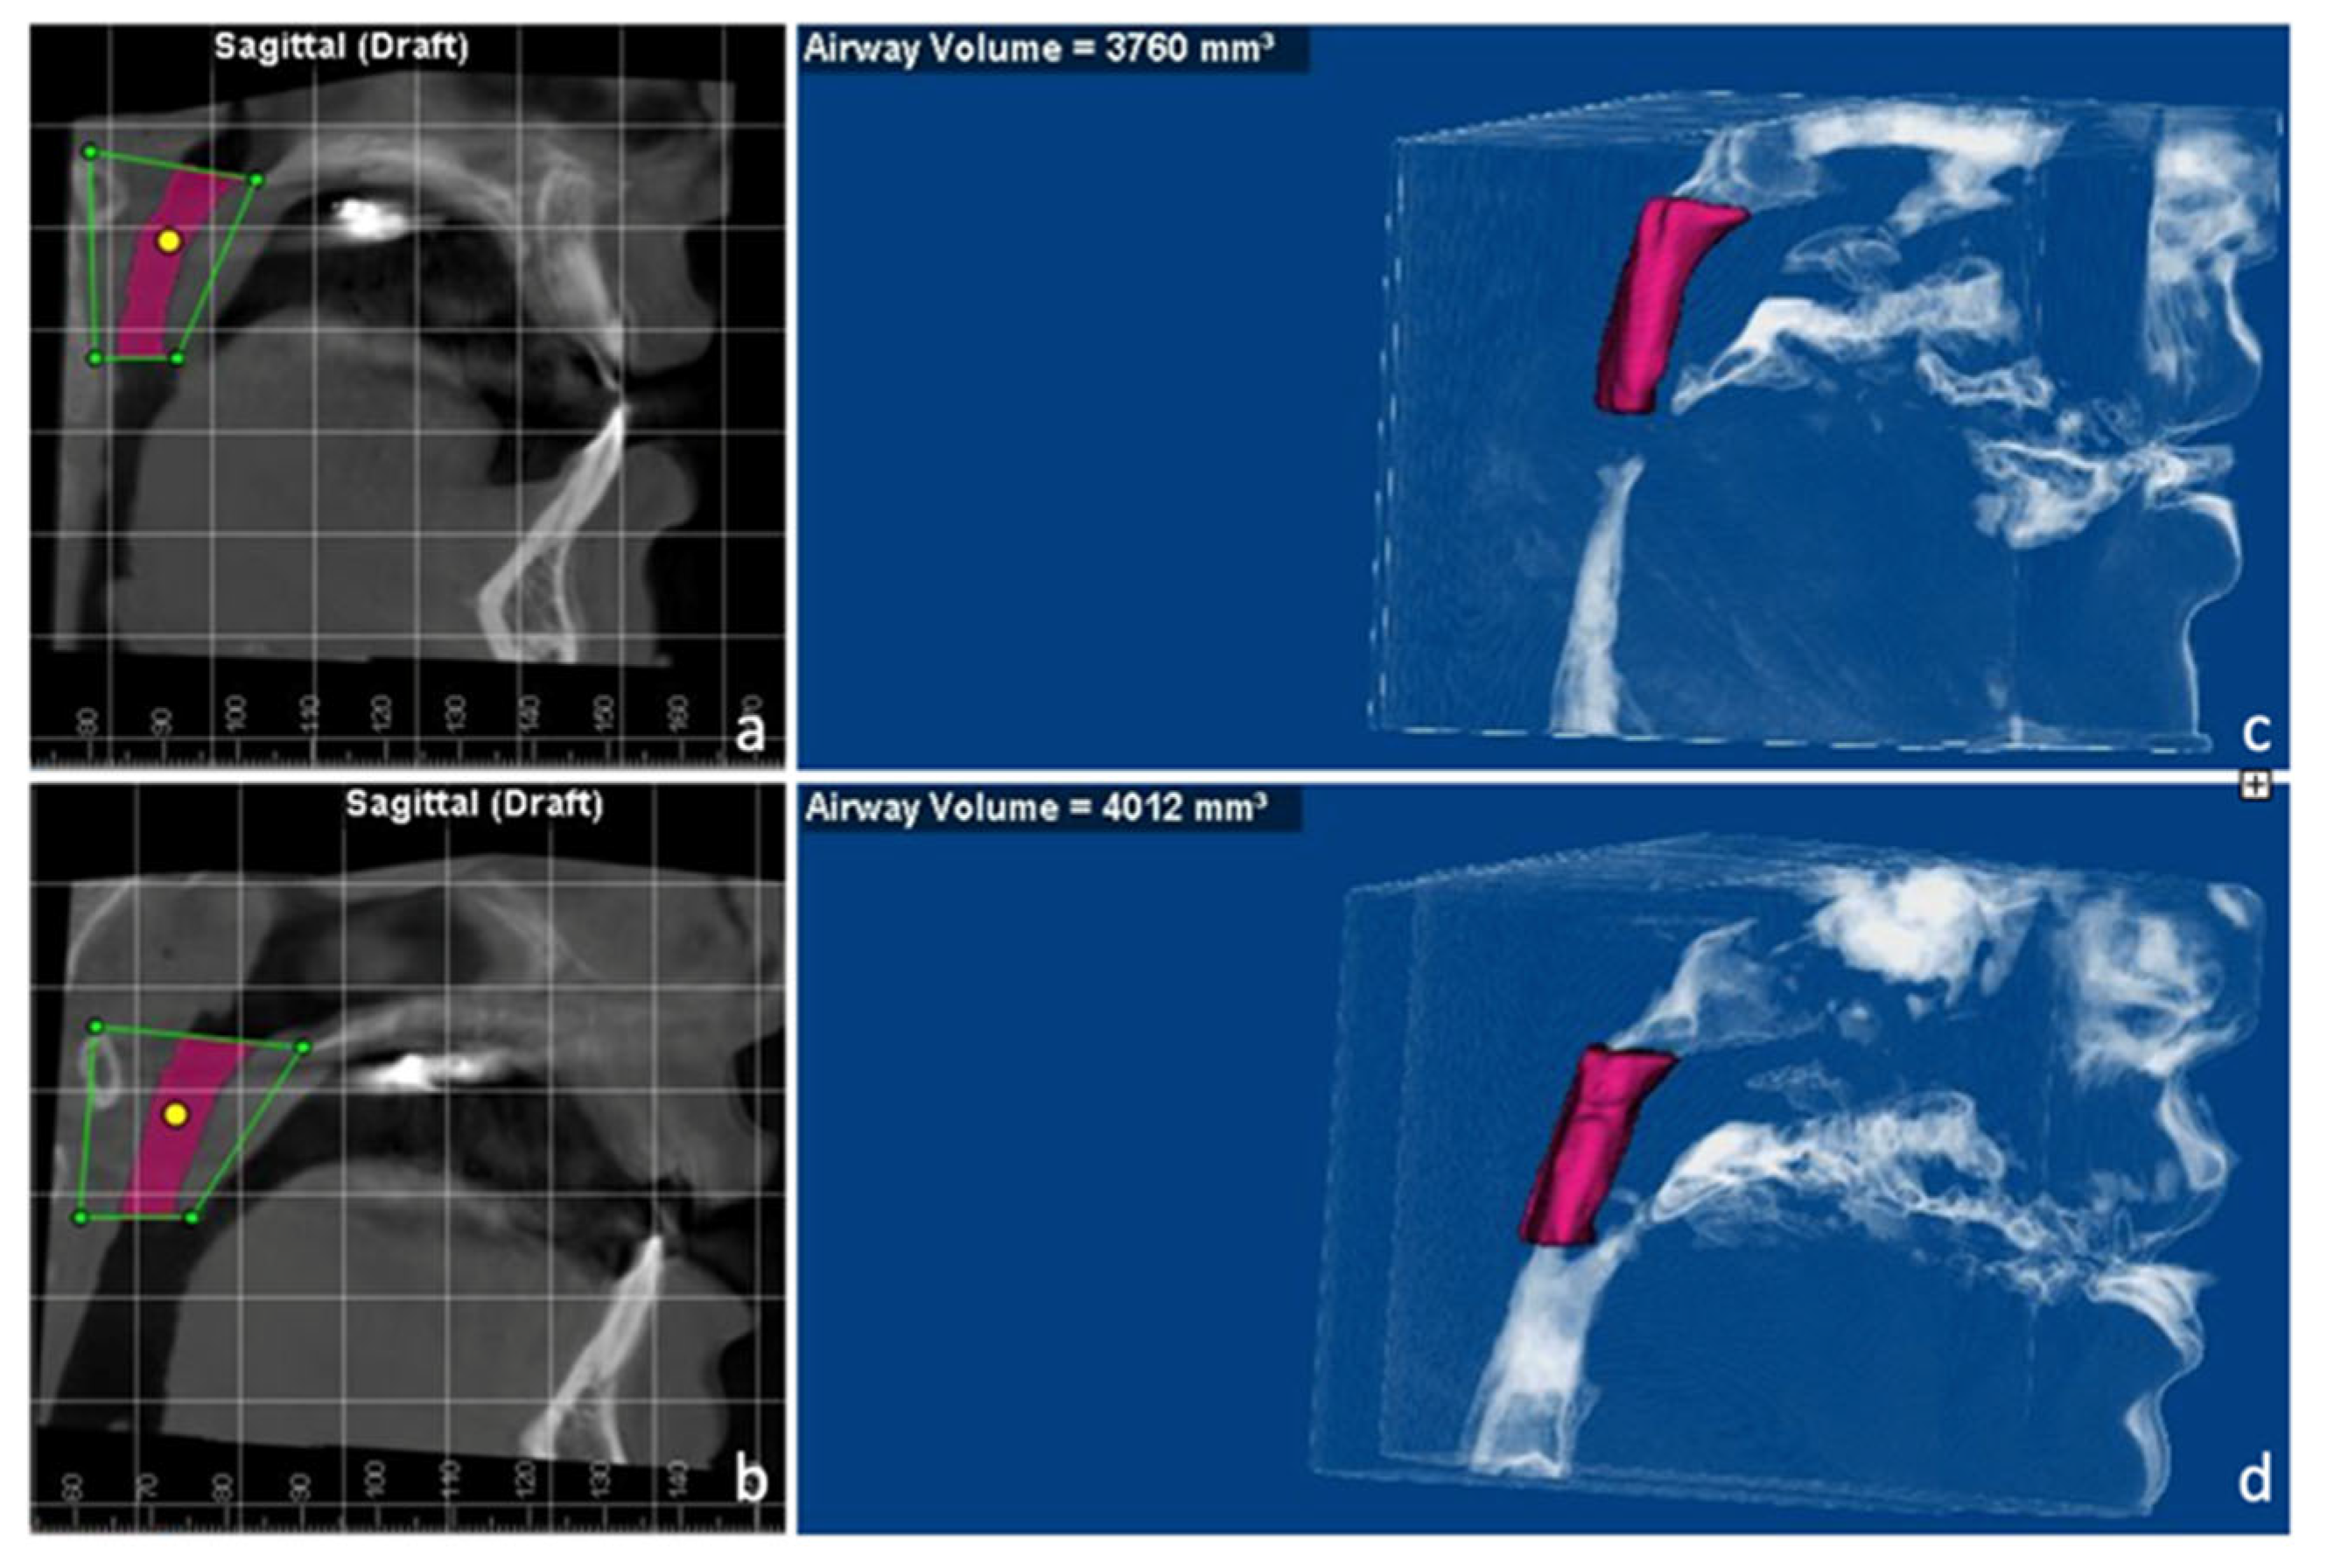

2.3. Treatment Progress

2.4. Treatment Results